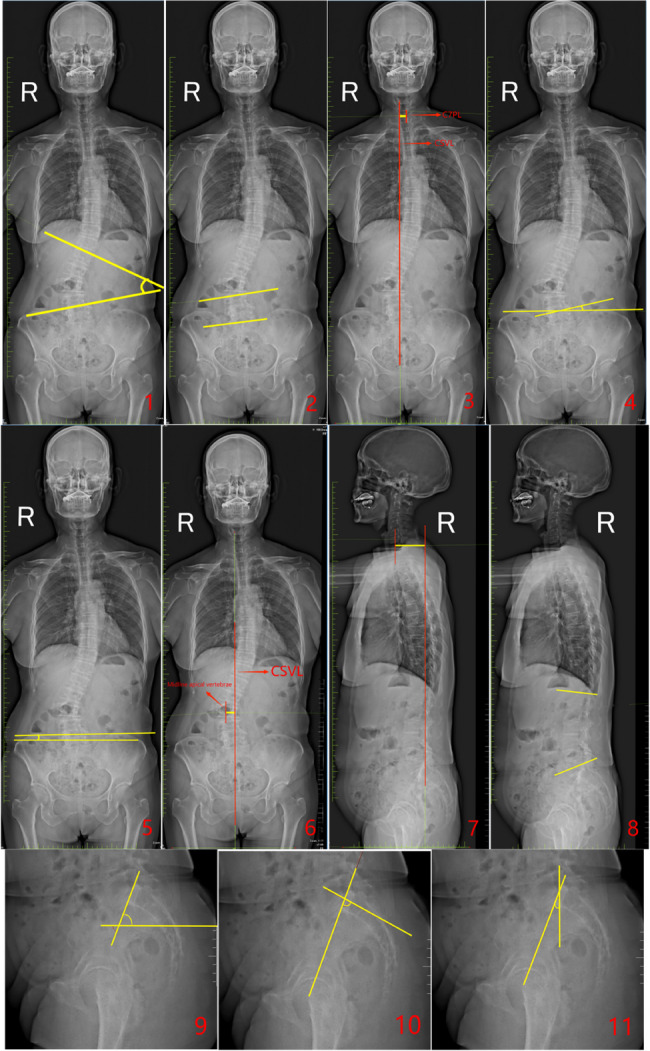

In this study, we utilized X-ray imaging equipment (an ED150L X-ray machine provided by Tshima, Japan) for a full-length spinal examination. All patients underwent standing full-length spinal imaging with their arms supported on a frame, shoulders flexed forward at 30°, and elbows slightly bent (see Fig. 1).

- Major Curve (MC): The angle between the tangents of the superior endplate of the uppermost vertebra and the inferior endplate of the lowermost vertebra in the major coronal curve of the spine.

- Fractional Curve (FC): The angle formed between the tangent of the superior endplate of L4 and the superior endplate of S1 in the lower curve of the spine on the coronal plane.

- Coronal Balance Distance (CBD): The horizontal distance between the C7 plumb line (C7PL) and the central sacral vertical line (CSVL).

- Number of main curved vertebrae: The total number of vertebrae involved in the major curve, including the end vertebrae.

- L5 Tilt Angle (L5TA): The angle formed between the superior endplate of L5 and the line connecting the highest points of both iliac crests (all L5TA values in this study refer to preoperative measurements).

- Coronal Pelvic Inclination (CPI): The angle between the line connecting the highest points of the iliac crests and the horizontal plane.

- Apical Vertebral Translation (AVT): The horizontal distance from the midpoint of the apical vertebra (or disc) to the CSVL in the coronal plane.

- Apical Vertebral Rotation(AVR): Measured using the Nash-Moe method (refer to Fig. 2), classified into grades I, II, III, IV, and V.

- Pelvic Tilt (PT): In the sagittal plane, the angle between the line connecting the center of the femoral head and the midpoint of the superior endplate of S1, and the vertical line.

- Pelvic Incidence (PI): The angle formed between the line connecting the center of the femoral head to the midpoint of the S1 superior endplate and the line perpendicular to the superior endplate of S1 in the sagittal plane.

- Sacral Slope (SS): The angle between the horizontal line and the tangent to the S1 superior endplate in the sagittal plane.

- Lumbar Lordosis (LL): The angle formed between the superior endplate of L1 and the inferior endplate of L5 in the sagittal plane.

- Sagittal Vertical Axis (SVA): The horizontal distance between the C7PL and the posterior superior corner of the sacrum in the sagittal plane.